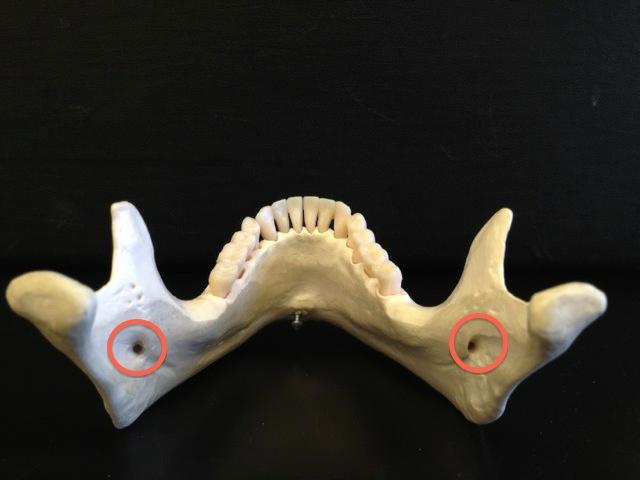

Type lV: residual vertical bone height of 10 mm or. As a conclusion, the configurations with a considerable (3 mm) height difference between quadrants of the mandible in the anterior segment showed the most successful results in the peri-implant bone. Decreased mandibular bone height at mandibular M1 may create a stress riser at this location, which along with thin cortical bone may explain why this is a common area for mandibular fracture. Type III: residual alveolar bone height of 11 to 15mm measured at the least vertical height of the mandible. Thin cortical bone overlying the mesial and distal roots of PM4 and the mesial root of M1 limits use of these areas for application of monocortical anchorage devices. Cortical bone thickness of 10 kg compared with the number of observations at the immediately mesial and distal locations. Resultsīuccal bone was generally thicker ventrally in the area studied with decreasing bone thickness over both roots of PM4 and the mesial root of the 1st molar (M1). The number of 3 mm increments were recorded as an estimation of mandibular height. On each image, bone thickness was measured along the buccal surface of both mandibles from the alveolar margin to the ventral border in 3 mm increments.

A split thicknss harvest tchnique is usd, which can yieId graft thicknesses f approximately 3 mm. The average thicknss of the parietaI bone is 7.45 mm. Anatomical position 3 (the location below the mental nerve) was found to be thinner than position 4 located proximal to it, contrary to any assumption that the. Sample Populationĭogs were distributed by weight into 3 groups (20 kg). Calvarial grafts are usually harvested in strips from the parietal bone. To characterize bone height and buccal cortical bone thickness of the caudal mandible of healthy dogs.